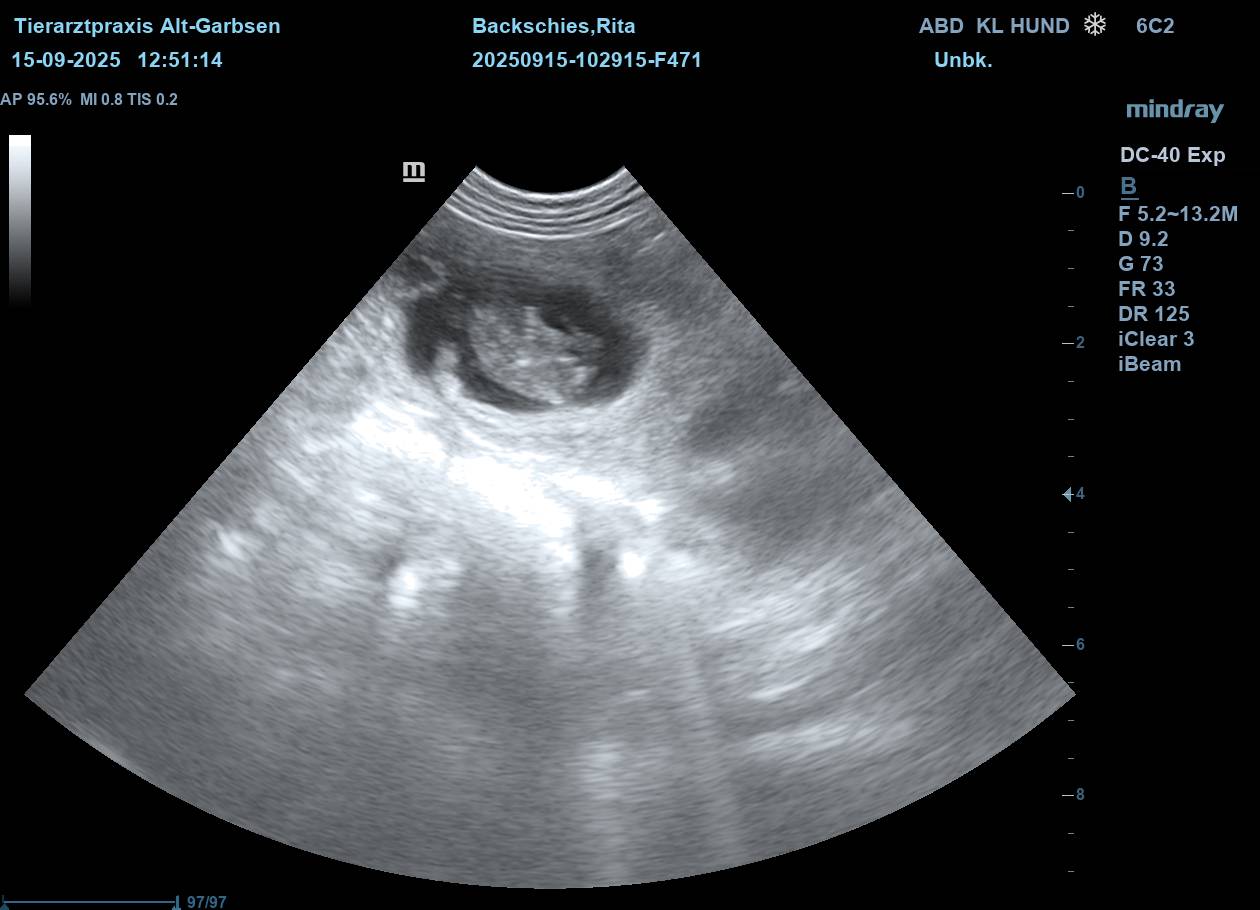

| Mo, 15.09.2025 | Es bahnt sich was an… der S-Wurf aus dem Zwinger Vom Lahberg FCI ist in die Produktion gegangen. Die Verpaarung am 17.08.2025 von Julissa Lisant Ingrid für Wambachtal „Rita“ und Kuddel vom Lahberg FCI war erfolgreich.🌿 Wir dürfen gespannt sein. In den nächsten Wochen werden wir dann Bilder vom wachsenden Babybauch posten. ![]() ![]() ![]() ![]() ![]() Jetzt heißt es mal wieder abwarten, beobachten, Däumchen drehen und hoffentlich bald freuen. |